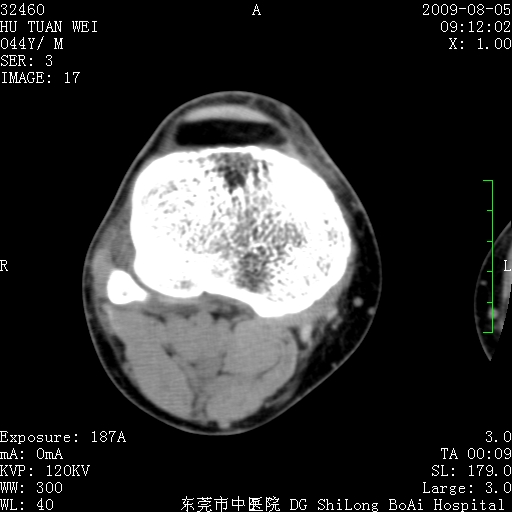

中年男性,膝韧带损伤术前检查!其他病史不清粗,不是我接手病人、且出院了!

1、股骨下段囊状膨胀性病变,边缘硬化明显,内多个残留骨棘呈多房型改变,囊腔密度较高无钙化,膝关节滑膜囊增厚,密度增高,关节腔少量积液。考虑:邻关节囊肿、退变性囊肿(软骨下囊肿)、着色性绒毛结节性滑膜炎、abc、骨巨、良性纤维组织细胞瘤等鉴。虽然年龄偏大,部位于骨端,但有外伤史,本人还是倾向于动脉瘤样骨囊肿(abc)可能性大。邻关节囊肿及软骨下囊肿次之考虑。

2、胫骨髁间棘撕脱骨折,交叉韧带损伤可能;

3、关节退行性改变。

病理结果:色素沉着绒毛结节性滑膜炎

感谢反馈病理结果!本病为慢性关节病变。以关节滑膜高度增生、绒毛结节形成伴含铁血黄素趁着为特点。病因:有炎症、肿瘤、外伤关节出血、代谢障碍、变态反应及感染等学说。增强扫描呈关节腔内单个或多个强化的软组织结节影或滑膜不规则增厚伴关节积液为本病的特征性表现。